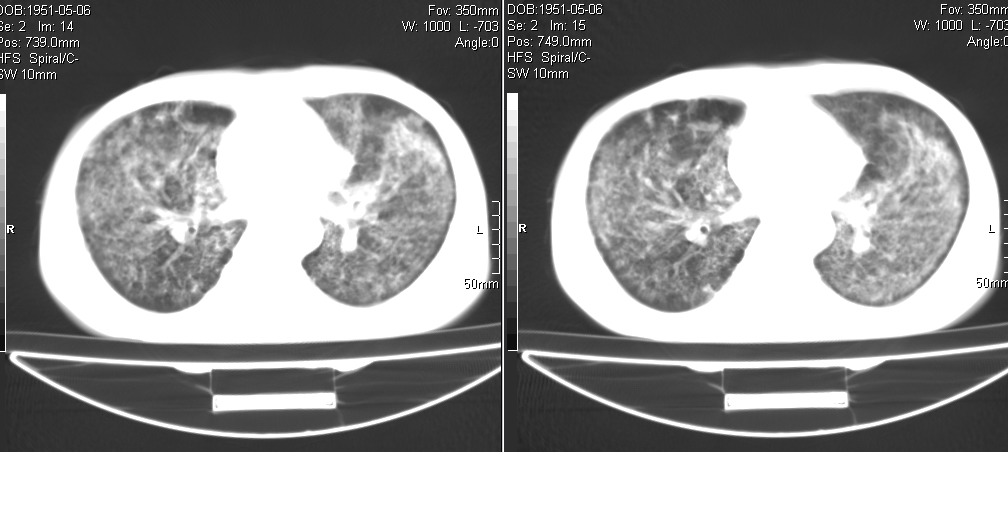

以下是引用光线在2008-5-6 18:36:00的发言:[br]双肺结核(左上肺空洞形成)、间质性改变合并感染,右肺大泡;右侧胸膜增厚。

以下是引用zsl6918在2008-5-7 1:54:00的发言:[br]首先肺泡蛋白质沉着症,其次考虑机遇性感染。